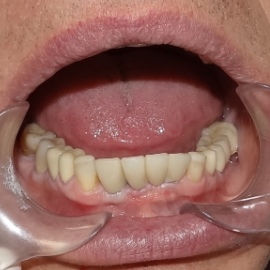

Bezzębie całkowite górne. Początkowo wykonane na mieście mosty całoceramiczne wydawały sie sukcesem, ale po roku pojawiły sie obrzęki i krwawienie z dziąseł. Pacjentka zgłosiła się do leczenia. Usunięto wszystkie zęby w szczęce. Sterowana regeneracja tkanek kości wyrostka, modelowanie kształtu i objętości tkanek miękkich, mosty porcelanowe przykręcane do implantów. Zadowalający wynik anatomiczny i estetyczny.